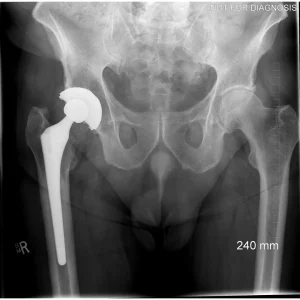

Revision Total Hip Replacement (Revision THA)

What Is a Revision Total Hip Replacement?

A revision total hip replacement (revision THA) is a surgical procedure performed to replace or repair a previous hip replacement that is no longer functioning well.

Clinical View